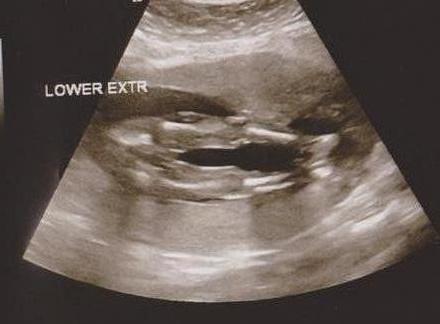

I don't really like the person that did my ultrasound. I only got 4 pics and 2 were profiles. Can anyone tell the gender from these?Attachment 4853Attachment 4854

Girl!

Girl

Girl~

Girl :babyf:

Girl, sorry you didn't like your US tech, it makes the whole experience bad when they dont seem to be very helpful and it is hard to find a good one.

Girl congrats

Thanks! everyone. She said girl but it was so quick and she did not print many pics. I am looking into a 4d place so maybe we can get better pictures and so we can enjoy getting to see our baby. It just seemed rushed and uninterested. Maybe I am just spoiled by my old ob and he did ultrasounds in office.

That's a girl! Congrats :)